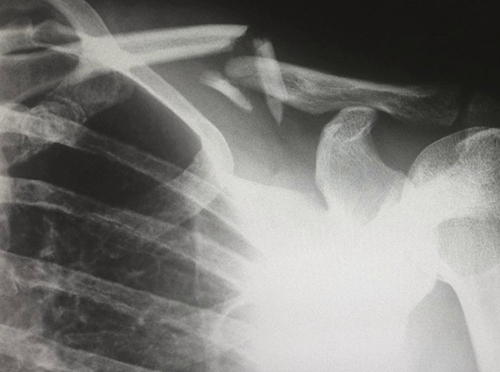

Ученые из Наньянского технологического университета в Сингапуре (NTU Singapore) разработали новый биоматериал, полностью сделанный из кожи лягушки-быка и рыбьей чешуи, который может помочь в восстановлении костей.

Пористый биоматериал действует как каркас для прикрепления и размножения костеобразующих клеток, что приводит к образованию новой кости. В ходе лабораторных экспериментов команда NTU Singapore обнаружила, что костеобразующие клетки человека, посеянные на каркас из биоматериала, успешно прикрепились и начали размножаться, что является признаком роста. Они также обнаружили, что риск воспалительной реакции на биоматериал невелик.

Такой каркас можно использовать для регенерации костной ткани, утраченной из-за болезни или травмы, например, дефектов челюсти в результате аварии или хирургического вмешательства при раке. Разработка также может использоваться для зубных имплантатов.